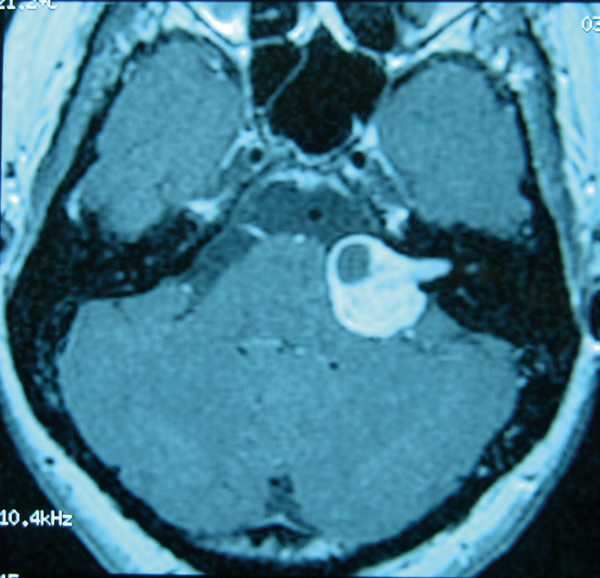

Figure 2: Gadolinium enhanced MRI scan showing a left vestibular schwannoma.

Imaging studies are not indicated unless tinnitus is unilateral, pulsatile, or there is asymmetric hearing loss or focal neurological abnormalities. Patients who report experiencing unilateral subjective tinnitus with or without hearing loss should undergo gadolinium enhanced MRI in order to exclude any cochlear or retrocochlear abnormality (Figure 2). Patients with pulsatile tinnitus should undergo CT angiography.